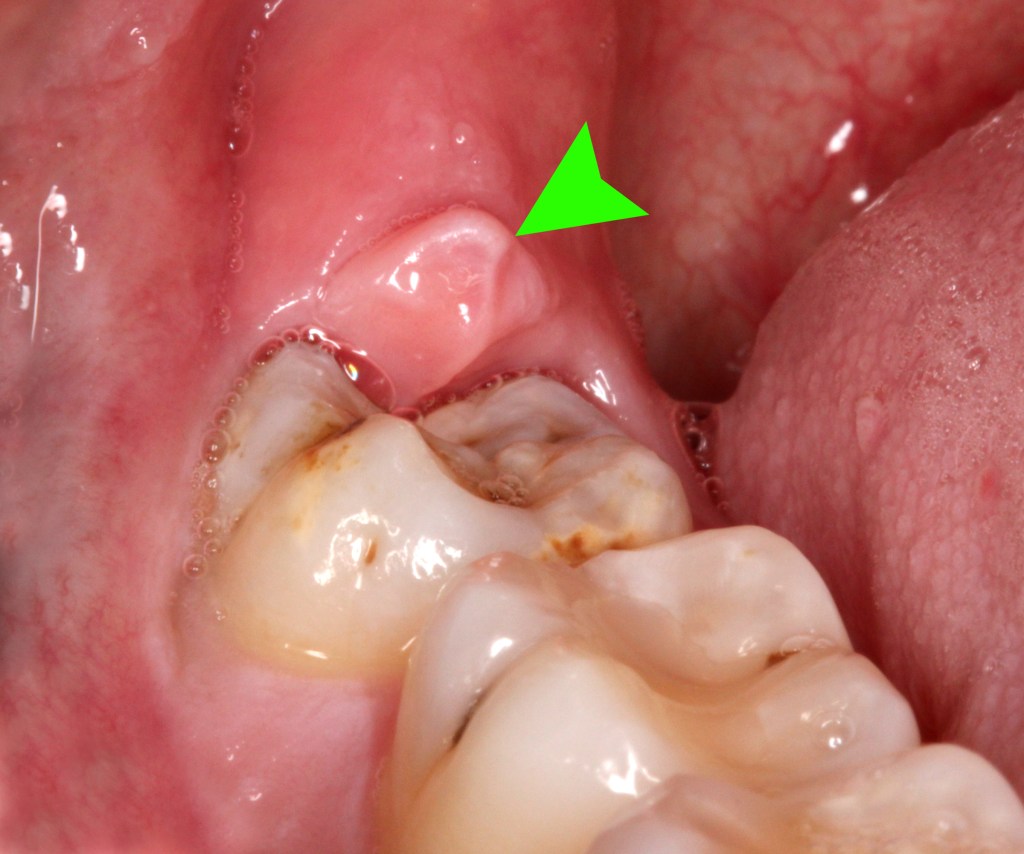

Pericoronitis is the inflammation of the gums above and around the tooth due to the overlying gum flap that causes chronic inflammation. This will result in a throbbing recurrent pain that will only resolve with the removal of the wisdom tooth.

Timely removal of the wisdom tooth is key to preventing unnecessary tooth loss.